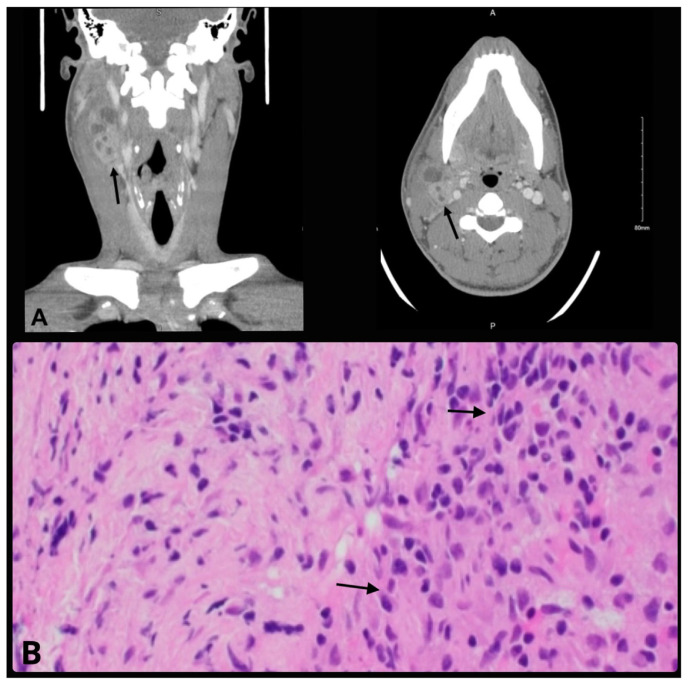

Lymphogranuloma venereum (LGV) is a sexually transmitted infection typically caused by serovars L1-L3 of Chlamydia trachomatis. These serovars are tissue-invasive with a preponderance for lymphatic spread and can be acquired via unprotected oral, anal, or vaginal sex. We present the case of a 23-year-old with a prior history of syphilis admitted with four weeks of progressively enlarging painful right cervical lymphadenopathy. Extensive testing, including oropharyngeal swabs and microbiological testing, did not yield a diagnosis, nor did extensive pathological and microbial testing of the lymph node biopsy tissue. Serological test of lymphogranuloma venereum revealed positive Chlamydia trachomatis L1 serovar antibodies. The patient had a complete resolution of his symptoms after three weeks of doxycycline therapy.